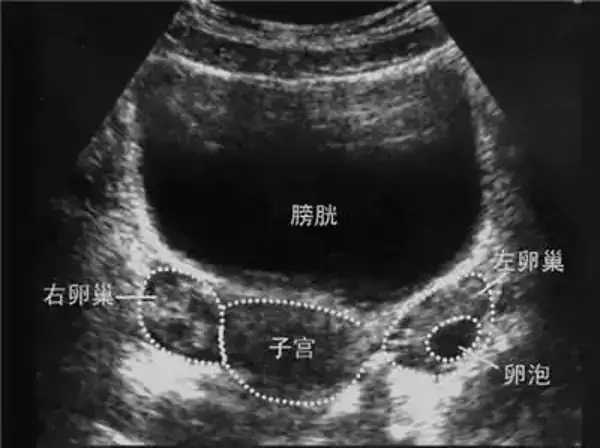

卵泡是由卵子及其周围的卵泡细胞组成,正常女性每个月都会有卵泡发育,能够发育成熟的就是我们所说的优势卵泡。一般来说女性朋友可以通过B超监测卵泡的生长,这时就可以判断是否有优势卵泡的发育了。

正常周期中,在B超的影像图中,卵泡为边界清晰的圆形无回声区,从周期的第5~6天卵泡直径约为5~7mm,第10天时卵泡直径可达10mm,此时超声已能清晰显示。正常周期中卵泡发育的速度比较恒定,约1~3mm/d,最快可达4mm/d,愈临近排卵期,增长愈快,排卵前5小时可增长7mm。

当卵泡直径>10mm时,称优势卵泡;卵泡直径达>18mm时,称成熟卵泡。

1、卵泡最大直径达20mm,优势卵泡最大直径范围为17~24mm,体积2.5~8.5mm3。径小于17mm者为非成熟卵泡;

2、卵泡外形饱满呈圆形或椭圆形,内壁薄而清晰,或可见内壁卵丘所形成的一金字塔形的高回声,多在排卵前24~30小时易于显示。亦可见优势卵泡周围有一低回声晕(多由排卵前卵泡膜组织水肿所致);

3、卵泡位置移向卵巢表面,且一侧无卵巢组织覆盖,并向外突出。